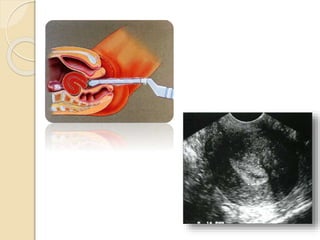

• 51.

• 52.

Los ovarios sonórganos elipsoides localizados en la fosita ovárica situada en la pared pélvica externa. Limitan con la fosa ovárica el uréter y la arteria ilíaca interna por detrás y la vena iliaca externa por arriba.

• 53.

El ecodoppler seagrega a la ecografía para detectar vascularización arterial y venosa, cuantificación de la misma y dirección. Para la mayoría de los autores el ecodoppler T.V. muestra buenos resultados en la diferenciación de las tumoraciones.